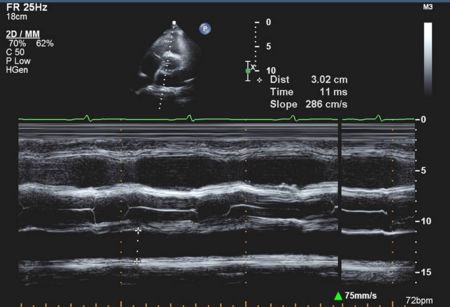

Mitral Valve M-mode Analysis

- Anterior leaflet with E/A appearance of diastology

- Decreased EF slope in MS

M Mode in Mitral Stenosis

- Leaflet tips bright (calcified) and thickened

- E/F slope decreased